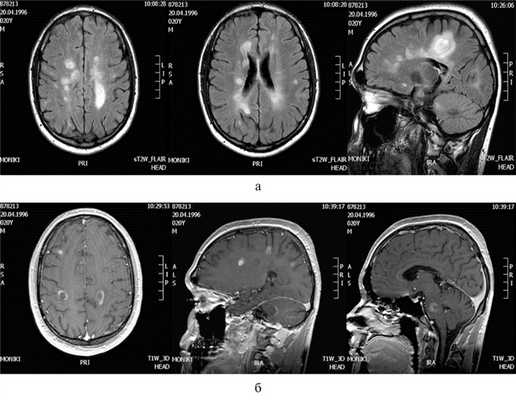

Оба эпизода острых психотических нарушений были связаны с обострениями РС и наличием множественных обширных очагов с признаками нарушения целостности ГЭБ. Учитывая увеличение частоты и выраженности обострений (нарастание показателя по EDSS на 3,5 балла), наличие психотических расстройств, которые при предыдущих экзацербациях никогда не фиксировались, а также выявление множества очагов, накапливающих гадолиний, состояние пациентки было расценено не просто как возобновление активности РС на фоне прекращения терапии ФГ, а как ребаунд-феномен [13, 14]. Пульс-терапия метилпреднизолоном оказалась не только малоэффективной, но и усилила при втором эпизоде психотические проявления. Только комплексная терапия, включающая в себя использование ГКС, плазмафереза и длительного курса нейролептиков, позволила достичь частичного терапевтического эффекта.

В декабре 2016 г. (через 1 мес) после перенесенной вирусной инфекции появились жалобы на слабость и онемение в правой половине тела, нарушение координации, психотические нарушения. Пациент был дезориентирован в пространстве и времени, не узнавал мать, звонил ей по телефону, просил прийти к нему, хотя мать в это время находилась рядом, пытался вырваться, встать с постели. Продуктивному контакту был мало доступен, взгляд настороженный, приступы агрессии сменялись плачем. По данным МРТ головного мозга с контрастным усилением (27.12.16): множественные очаги демиелинизации, 16 активных очагов с кольцевидным и диффузным типом накопления, появление множества новых очагов, увеличение в размерах прежних очагов (рис. 2). Рис. 2. МРТ головного мозга больного П. (обострение). а — Т2-ВИ, FLAIR; б — Т1-ВИ, контрастирование гадолинием.